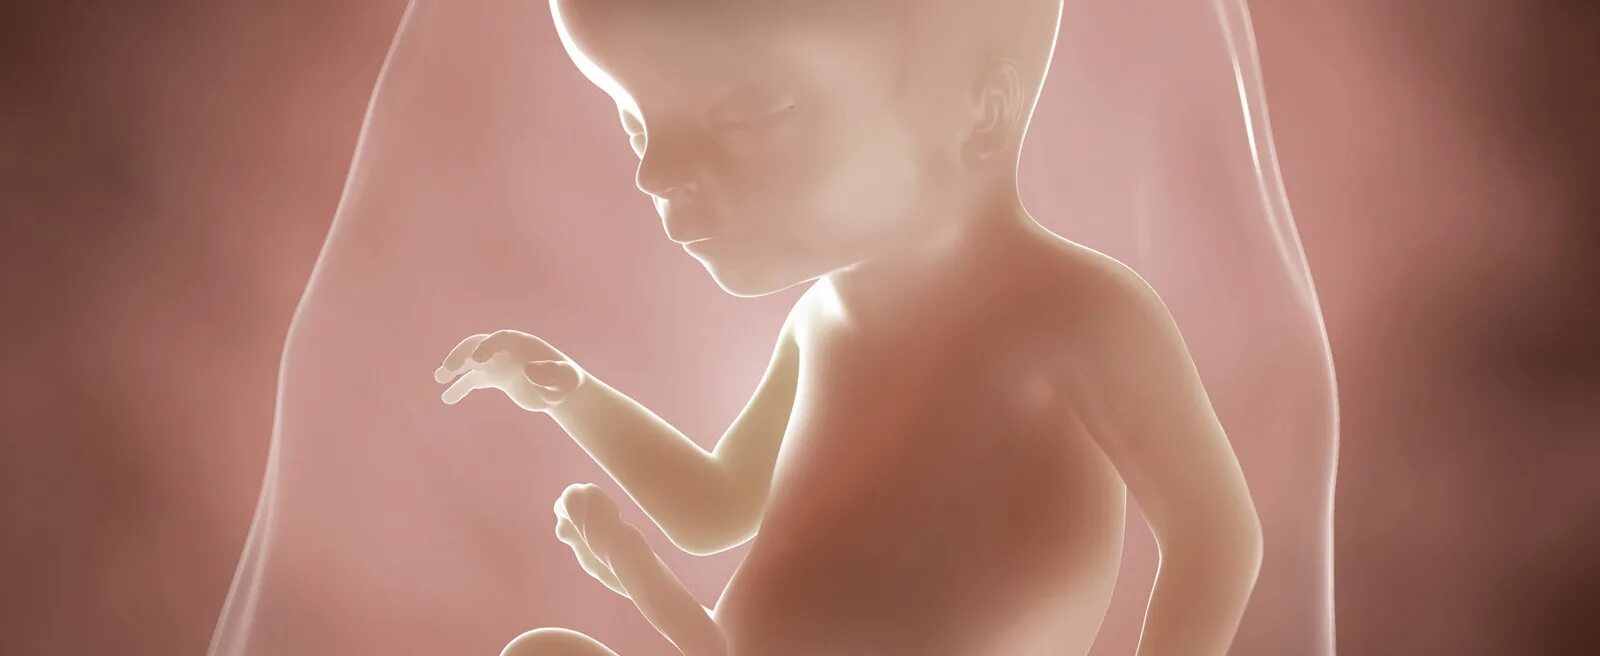

Как выглядит ребенок в 18 недель